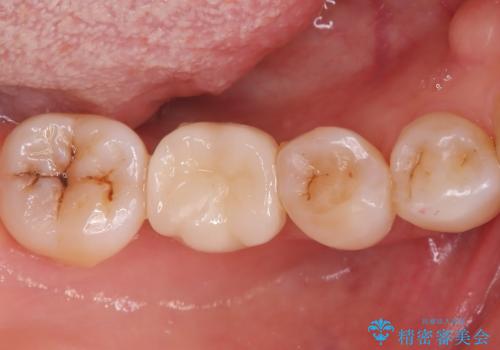

虫歯を治したい〈セラミック〉

奥歯に虫歯があると言われた セラミッククラウンでキレイで長持ちする歯へ

担当医 榊原康平